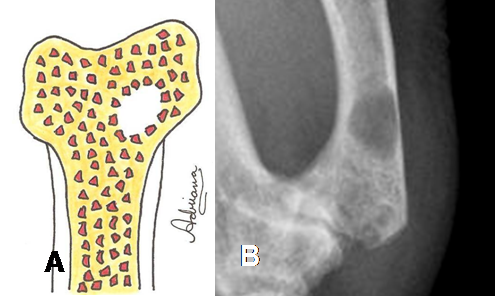

Fig 27. Lesión geográfica tipo 1B.

A: Diagrama de lesión bien definida, sin bordes escleróticos.

B: Rx AP. Imagen bien definida, pero de bordes no escleróticos por quiste óseo.